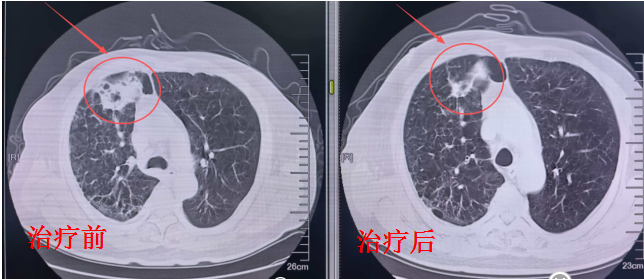

2. 喉部病灶:直线加快器——控瘤同期保功能

喉部病灶的诊治,则接纳了直线加快器。通过多叶准直器收尾三维适形调强放疗,射线可精确“塑形”,均匀隐蔽喉部肿瘤,同期灵验躲避食管、气管等弥留器官。

在高效边界局部病灶的同期,最猛进度保留患者的吞咽、发声功能,保险后续生计质料。

喉部复查